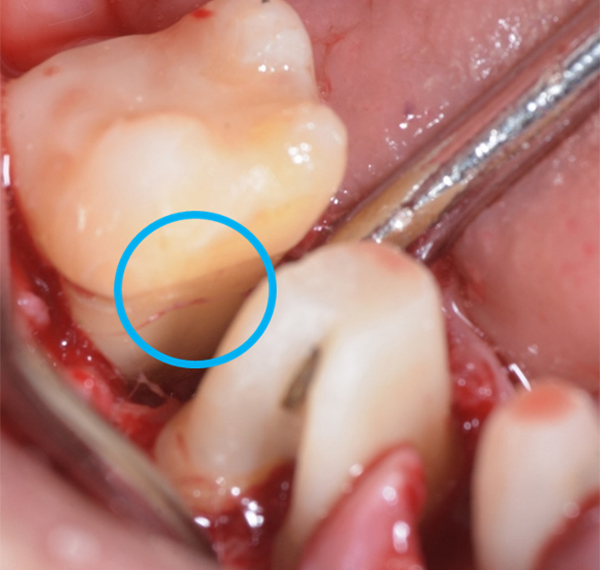

軽度〜中程度レベルの歯周炎であれば、ここで改善が見られますが、中程度以上の歯周炎の場合は、その後に歯周外科処置を行うことが多いです。なぜなら、歯周ポケットが5mm以上ある部位にSRPを行っても多くの歯石の取り残しがあるという報告があるため、深い歯周ポケットを有する患者さんに対しては歯周外科処置を行います。歯周外科処置で一般的な術式は歯肉剥離掻爬術です。痛く無いように麻酔(局所麻酔)をした後、歯肉をメスで切り(切開)、切った歯肉を骨から剥がし(剥離)、歯の根に付着した歯石、歯槽骨の形態などが直接見える状態で、歯石や感染物の除去を行います。その際必要であれば、その後に患者さん自身で清掃がしやすいように骨の形態を整える歯槽骨整形も行います。最後に切った部分を縫って(縫合)処置を終わります。

歯周組織再生療法といい、先に記しました通り、GTR法、エムドゲインを使用した方法、リグロスを使用した方法といくつかあります。GTR(Guided Tissue Regeneration)法とは、歯周外科処置と同様に歯肉をメスで切り(切開)、切った歯肉を骨から剥がし(剥離)、歯の根に付着した歯石、歯槽骨の形態などが直接見える状態で、歯石や感染物の除去を行います。その後、骨が吸収して失われた部分にこのバリア膜で覆い縫って(縫合)処置を終わります。バリア膜で覆うことで、歯肉などの軟組織が骨の中へ直接入り込むことを防ぎ、新しい血管が新生され、歯周組織の再生を促します。治療後およそ6ヶ月待ちます。